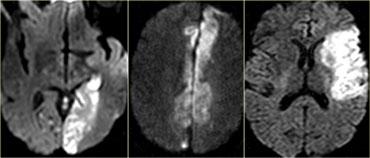

Hình ảnh Khuếch tán (DWI)

DWI là chuỗi xung nhạy cảm nhất trong chẩn đoán hình ảnh đột quỵ.

DWI nhạy cảm với sự hạn chế chuyển động Brown của nước ngoại bào do mất cân bằng gây ra bởi phù độc tế bào.

Bình thường, các proton nước có khả năng khuếch tán ra ngoài tế bào và mất tín hiệu.

Tăng tín hiệu trên DWI cho thấy sự hạn chế khả năng khuếch tán ngoại bào của các proton nước.